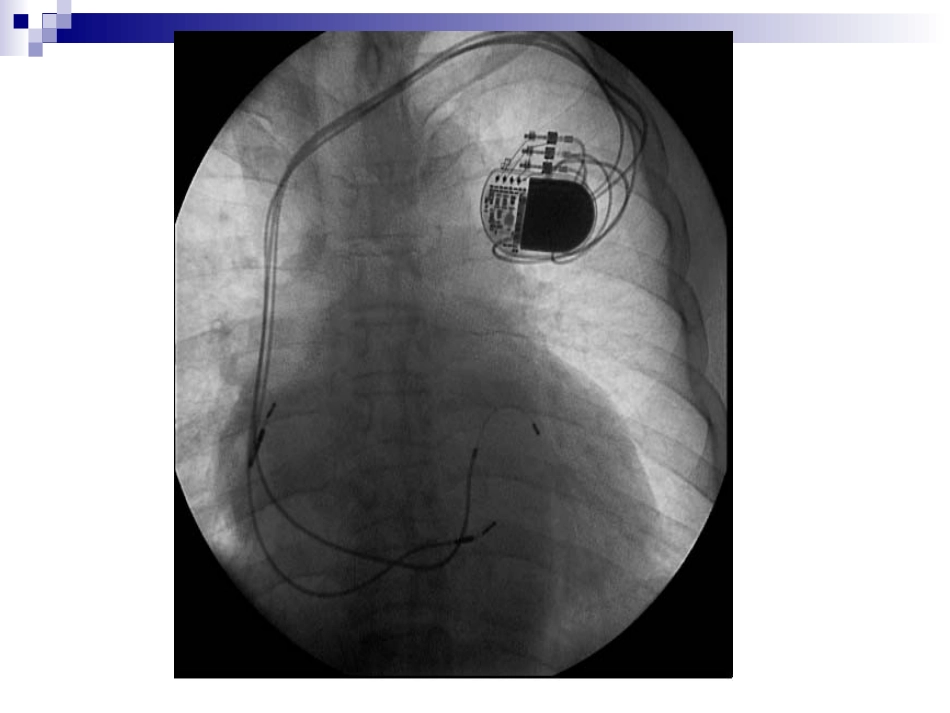

心脏起搏器心脏起搏定义人工心脏起搏(artificialcardiacpacing)是通过人工心脏起搏器或程序刺激器发放人造的脉冲电流刺激心脏,以带动心脏搏动的治疗方法。主要用于治疗缓慢心律失常,也用于快速的心律失常和治疗。什么是心脏起搏器?心脏起搏器由脉冲发生器、导线和电极组成。脉冲发生器呈扁圆形,体积非常小,大约有40506毫米,重量约30克。它实际上是一个微型计算机,由高性能电池提供能量。起搏器通常埋植在上胸部的皮下,它的导线通过静脉到达心脏,导线顶端的电极固定在心脏的内侧面心肌上。起搏器工作时,脉冲发生器发出的电脉冲,经导线、电极传到心肌,心肌感受到电脉冲刺激产生收缩。同时,起搏器电极也将心脏的电活动收集起来存入脉冲发生器内的芯片内,以便进行分析。人工心脏起搏器工作原理:监测心电、电激心脏临床上广泛应用的人工心脏起搏:就是用低能量电脉冲暂时或长期地刺激心脏,使之发生激动,以治疗严重心动过缓,心脏起搏也可用以终止或控制室上性和室性快速心律失常,称为抗心动过速起搏。心脏起博器的功能能替代或补充正常激发和控制心脏收缩的生理电子系统。它通过周期性发放的电脉冲刺激心脏,引起心搏,并实现生物机能控制。如果心脏原有的起搏点丧失其作用而使冲动形成受扰,或者心脏固有的传导系统不能正常工作(如窦性停止、窦房阻滞、窦性心动过缓或某心房、心室出现异使节律,以及心动过速等),起搏器能帮助心脏恢复、接近正常功能。特别是对那些药物疗效不佳,甚至于治疗无效的心脏病患者,人工心脏起搏器在临床上获得了成功。绝大多数起搏器具有四个功能刺激心脏使它除极感知心脏自身电活动对增加的新陈代谢需求作出反应,提供频率适应性起搏提供由起搏器存储起来的心电诊断信息心脏起搏器的临床应用长期起搏房室传导阻滞三束支阻滞伴心脑综合症病态窦房结综合症临时性起搏指心脏病变可望恢复,紧急情况下保护性应用和诊断应用的短时间使用心脏起搏诊断:还可用于某些疾病的诊断。例如心房调搏辅助诊断可疑的冠心病、心房超速起搏法诊断窦房结功能不全,预测完全性房室传导阻滞患者是否有发生心脑综合症的危险等。药理及实验研究:人工心脏起搏技术在心血管的生理和病理生理以及药理和临床应用的实验研究工作中,也取得了发展。例如在心律失常方面,将逐步揭示一些我们还不能解释的电生理现象,对心律失常的诊断和治疗会起到更积极的作用。永久性与临时性心脏起搏器埋藏于体内的起搏器为埋藏式起搏器,作为永久性心脏起搏,用于慢性或间歇发作的严重缓慢性心律失常如心脏传导阻滞、病态窦房结综合征等;放在体外的起搏器为体外起搏器,用于临时性起搏,如永久性起搏器植入的过渡或心脏骤停的抢救等等。临时起搏的适应征1.急性前壁心肌梗塞伴有Ⅲ度或高度房室传导阻滞,或下壁梗塞伴有Ⅲ度或高度房室传导阻滞经药物治疗无效者。2.急性心肌炎或心肌病伴有阿斯综合征者3.药物中毒引起的心动过缓,并发阿斯综合征者.4.心脏手术后发生的Ⅲ度房室传导阻滞者5.电解质紊乱,如高血钾引起的Ⅲ度房室传导阻滞者。6.超速起搏用以诊断及治疗其他方法所不能解决的室上速或室性心动过速。7.保护性应用于更换永久起搏导管前,冠脉造影,电击复律,外科手术等。强干扰信号对起搏器的影响当患者处于较强的50Hz市电或高频强电磁场干扰的环境中时,如果这些干扰信号很强,频率远高于起搏频率,这些干扰信号和感知的R波一样,能使按需功能控制器的单稳态电路提前触发;脉冲发生器在干扰信号存在的时间内一直处于抑制状态,致使起搏器停止发放起搏脉冲,从而使患者失去人工心脏起搏。解决方法?解决方法保持在强干扰存在的条件下,把强干扰信号衰减,使之不能触发按需功能控制器,失去对脉冲发生器的抑制作用,脉冲发生器按自己固有频率发放起搏脉冲,起博器转换为固定式工作,其起搏频率稍快于按需型(这是扣除按需型的反拗期的结果)。强干扰一旦消失,起搏器又能自动恢复到按需工作状态。具体如何实现?最高起搏频率限制电路患者安装起搏器后的心率多数是依赖起搏器的工作频率,如果起搏器因电源、元器件变质或损坏而...